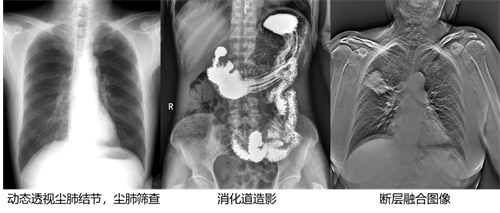

不同于常规静态DR只能进行平片摄影检查,动态DR可以实现多模态的检查。包括数字化摄影、数字化透视、数字化造影、可视化点片、尘肺筛查、断层融合功能检查、DSA功能检查、全脊柱及双下肢拼接检查、动态功能成像等多模态检查,相较于静态DR具有更加丰富的临床应用。不止可以应用于放射科,还可以应用于体检科、内科、外科、骨科、急诊科等,应用的科室更加广泛。

(上图取自安健科技动态DR腾灵系列影像)